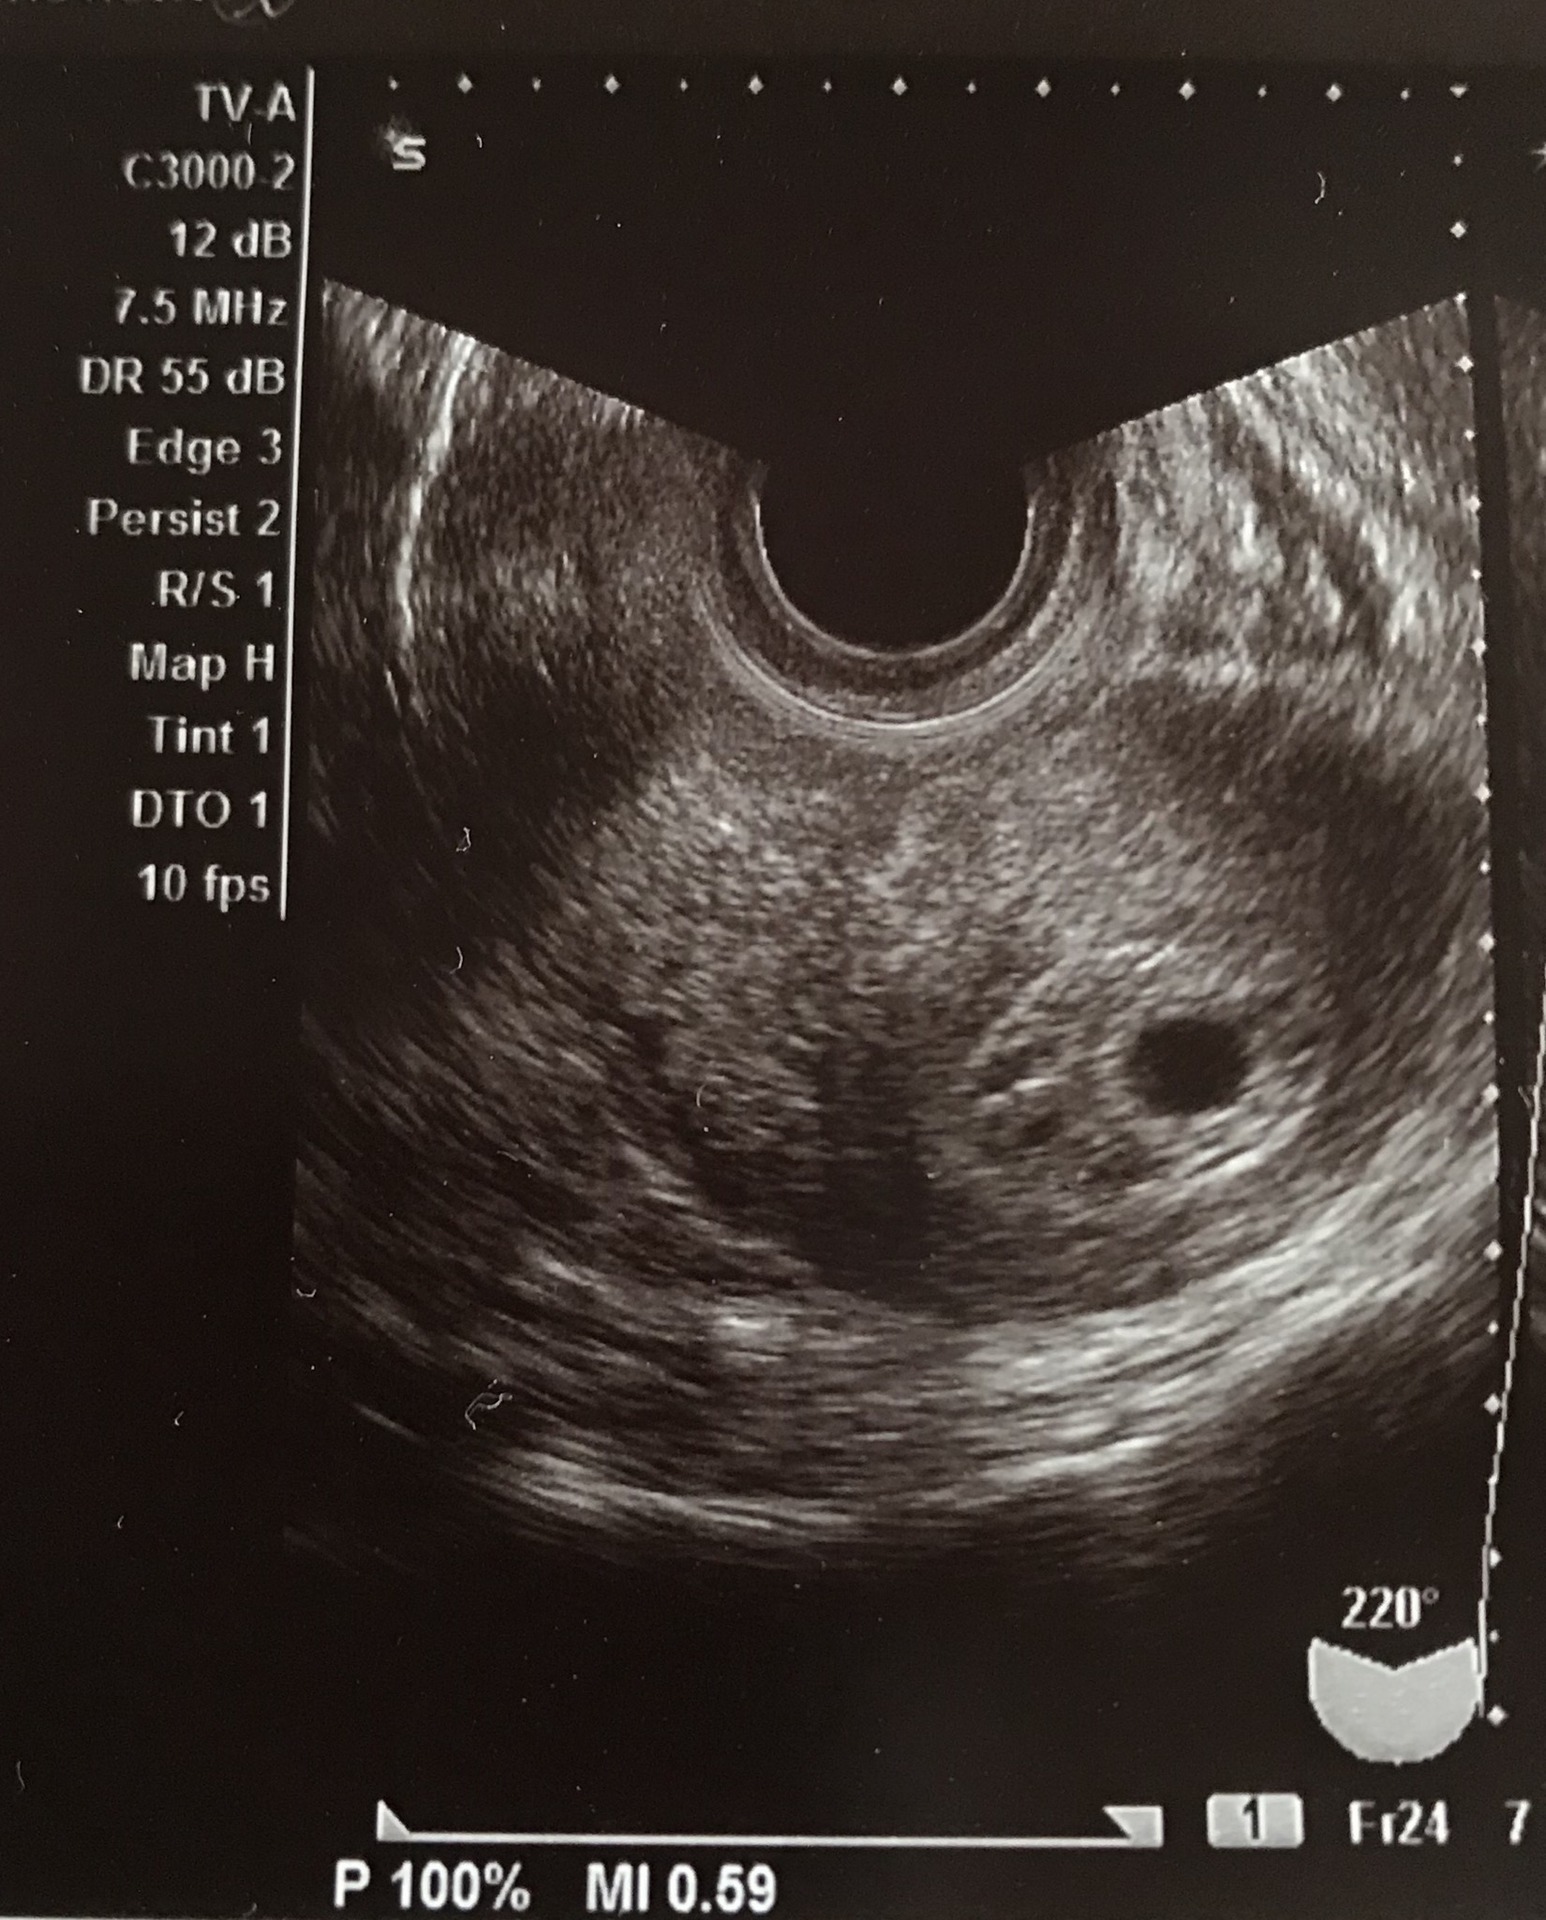

初めてパパ用 胎嚢 たいのう 超音波エコー検査の見方 6週0日 プレパパ獣医 子供と猫とrichになるブログ

5 産科一般超音波検査 初期編 正常所見4 7週 日本産婦人科医会

妊娠2ヶ月 妊娠4週0日 7週6日 の胎芽の超音波画像 2 超音波画像で見る妊娠各月の胎児